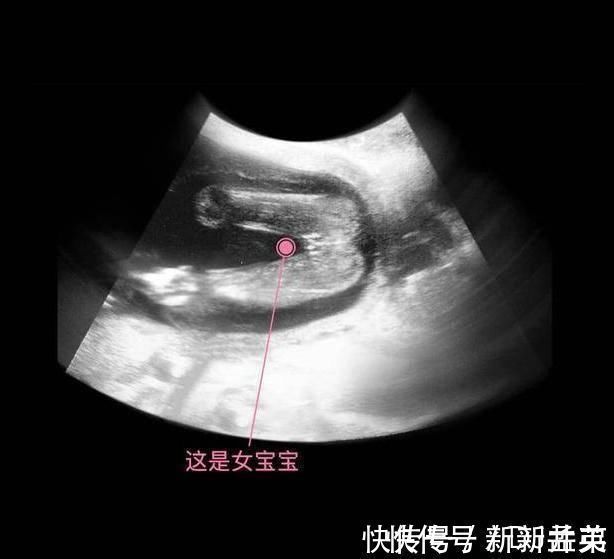

其实从孕9周开始,胎儿的性别就开始分化,孕17周,B超扫描清晰可见胎儿的性别,不过也有的宝宝因为胎位的原因,或者脐带遮挡,让医生产生了误判,男女会出现翻盘的可能呢。